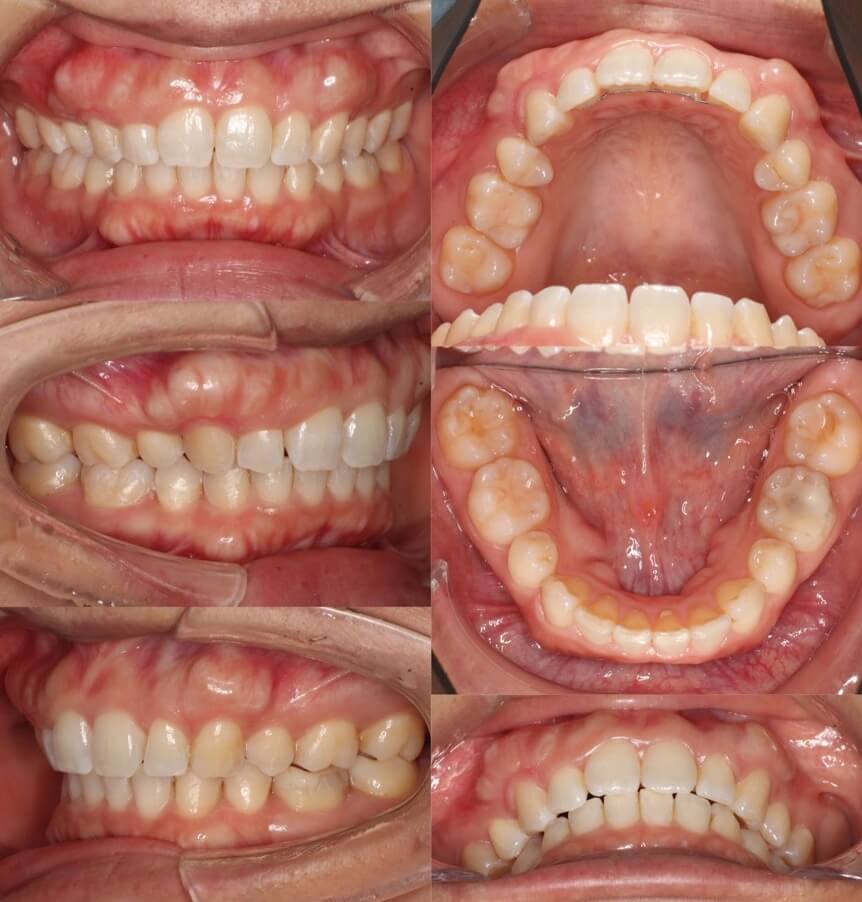

20代女性・マウスピース型装置

過蓋咬合の改善は見た目の変化は少ないのですが、口の中の歯並びの変化は大きいです。下の歯並びが見えるようになり正しいかみ合わせになりました。

<症例概要>

主訴:前歯のかみ合わせが悪い

年齢・性別:大学生女性

住まい:千葉県佐倉市

症状:過蓋咬合・右5番シザーズバイト・下顎叢生

治療方針:下顎前歯唇側傾斜による圧下

治療装置:マウスピース型矯正装置(アライナー装置)

アライナー枚数:43+27

治療期間:1年4か月

リテーナー:上下クリアタイプ

治療費用:990,000(税込)

代表的副作用:痛み・治療後の後戻り・歯根吸収・歯髄壊死・歯肉退縮

▶︎その他の副作用

【治療シミュレーション】

主に下の歯並びを前方に倒しながら歯茎方向に沈め(圧下)させ、過蓋咬合を改善していきます。

大学生男性・唇側矯正装置・4本抜歯